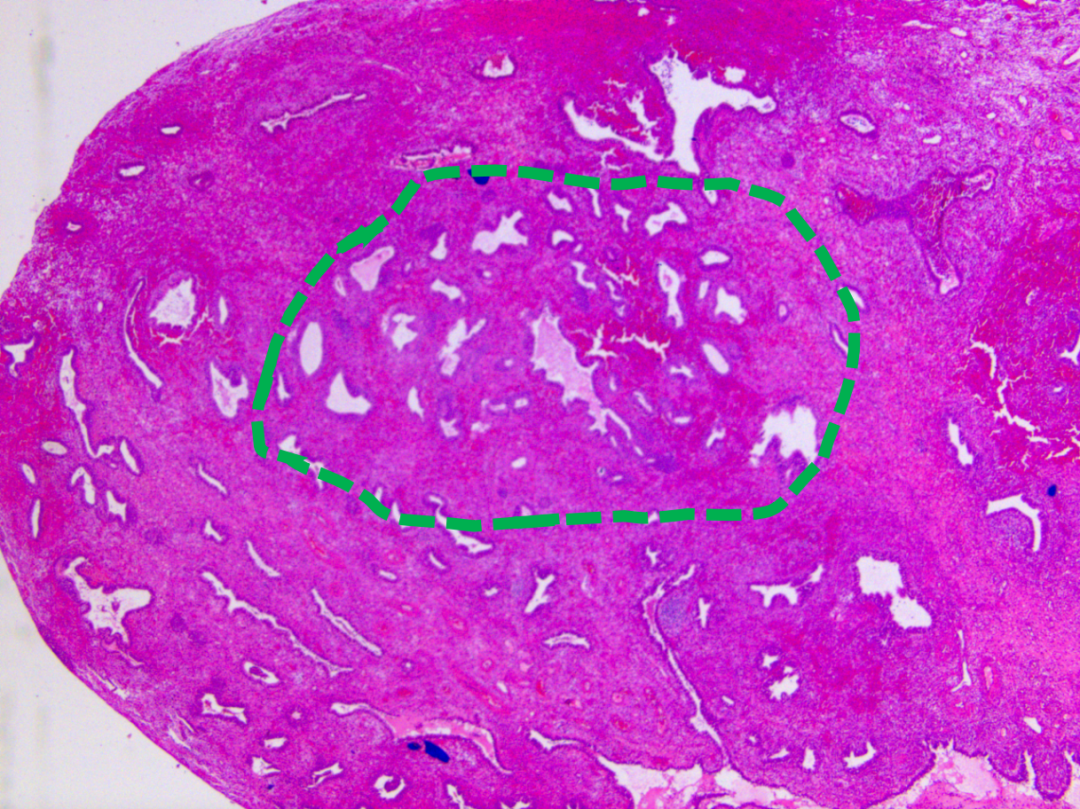

图示:低倍镜下局部腺体略显拥挤,形态不规则。

图示:息肉内部局部腺体略显密集(绿色虚线)。